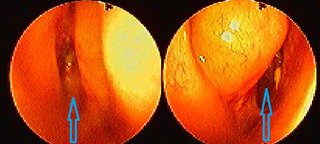

수술 후 빠른 재발이 일어나는 듯 합니다. ? ? 이렇게 빨리 코물혹이 재발 되리라,, 찾아오신 분들마다 ? 정말이지~ 많이 괴로워하시며.. 코물혹 수술은 안하고 싶으신 상황이십니다. ? [ 코물혹수술

잠실코모코한의원, 코물혹시술, 수술없이 코물혹을 치료합니다. ] 병원을 정말 가기 싫어하시는 아버님의~ 내원이 있으셨습니다. 코물혹이 있으시지만~ 큰 불편하심을 못느끼신다는.. 코물혹수술을 / 축농증수술을